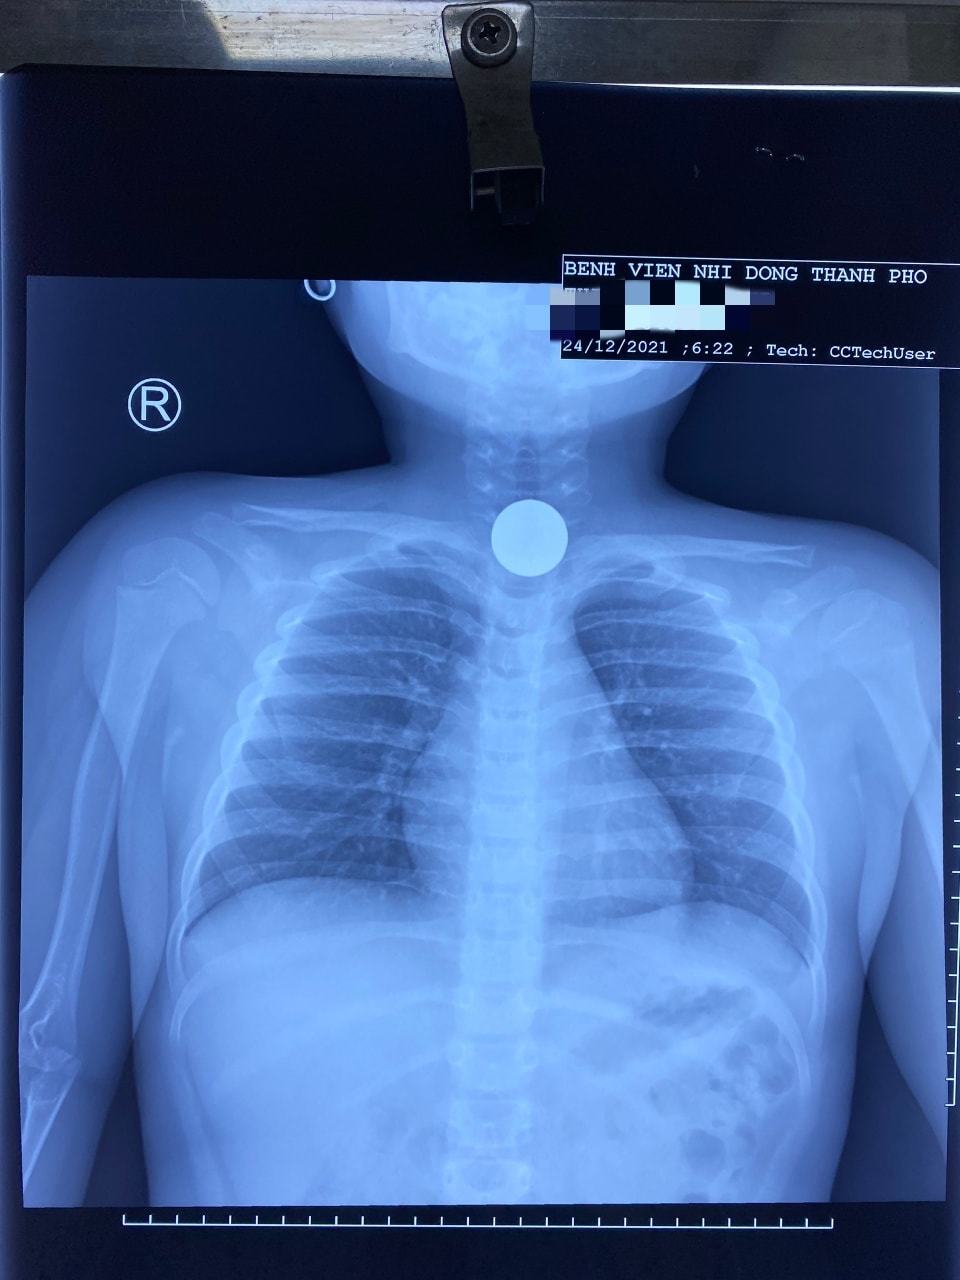

| Hình ảnh Xquang quan sát rõ dị vật chặn ở đường thở. Ảnh: BVCC |

Khi đến bệnh viện, bé vẫn vui chơi, tỉnh táo. Kết quả Xquang cho thấy, một vật cản âm tròn đều như mô tả đồng xu, mật độ như kim loại. Bác sĩ CK1 Lê Đức Lộc, Bệnh viện Nhi đồng Thành phố nhanh chóng được gọi vào viện, điều khiển ê-kip nội soi, gây mê và gắp được dị vật. Khi đó, đồng xu đã chặn ra khỏi đoạn 1/3 thực quản của bé.